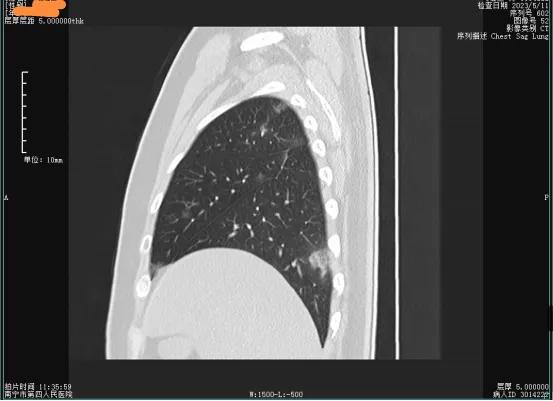

1、病毒残留:新型冠状病毒感染经过治疗后,患者肺泡组织内可能还存在极少量的新型冠状病毒,由于出院后停用相关治疗药物,这些少量潜伏的新型冠状病毒会再次复制,并在鼻咽部、咽拭子的复查时呈现阳性。此外,部分患者在肠道、粪便中也会残留少量失去活性的病毒,也会出现新型冠状病毒核酸检测阳性,但失活的病毒一般不具备致病和传染能力;